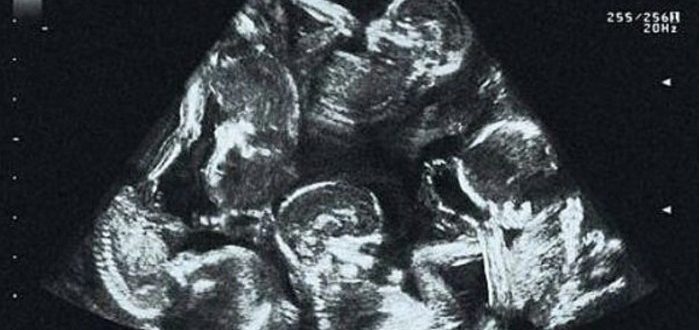

Anna hadde ventet på denne dagen med spenning og nervøsitet. Den andre ultralydundersøkelsen – den hvor man kan se babyen, høre hjerteslagene og finne ut om alt er